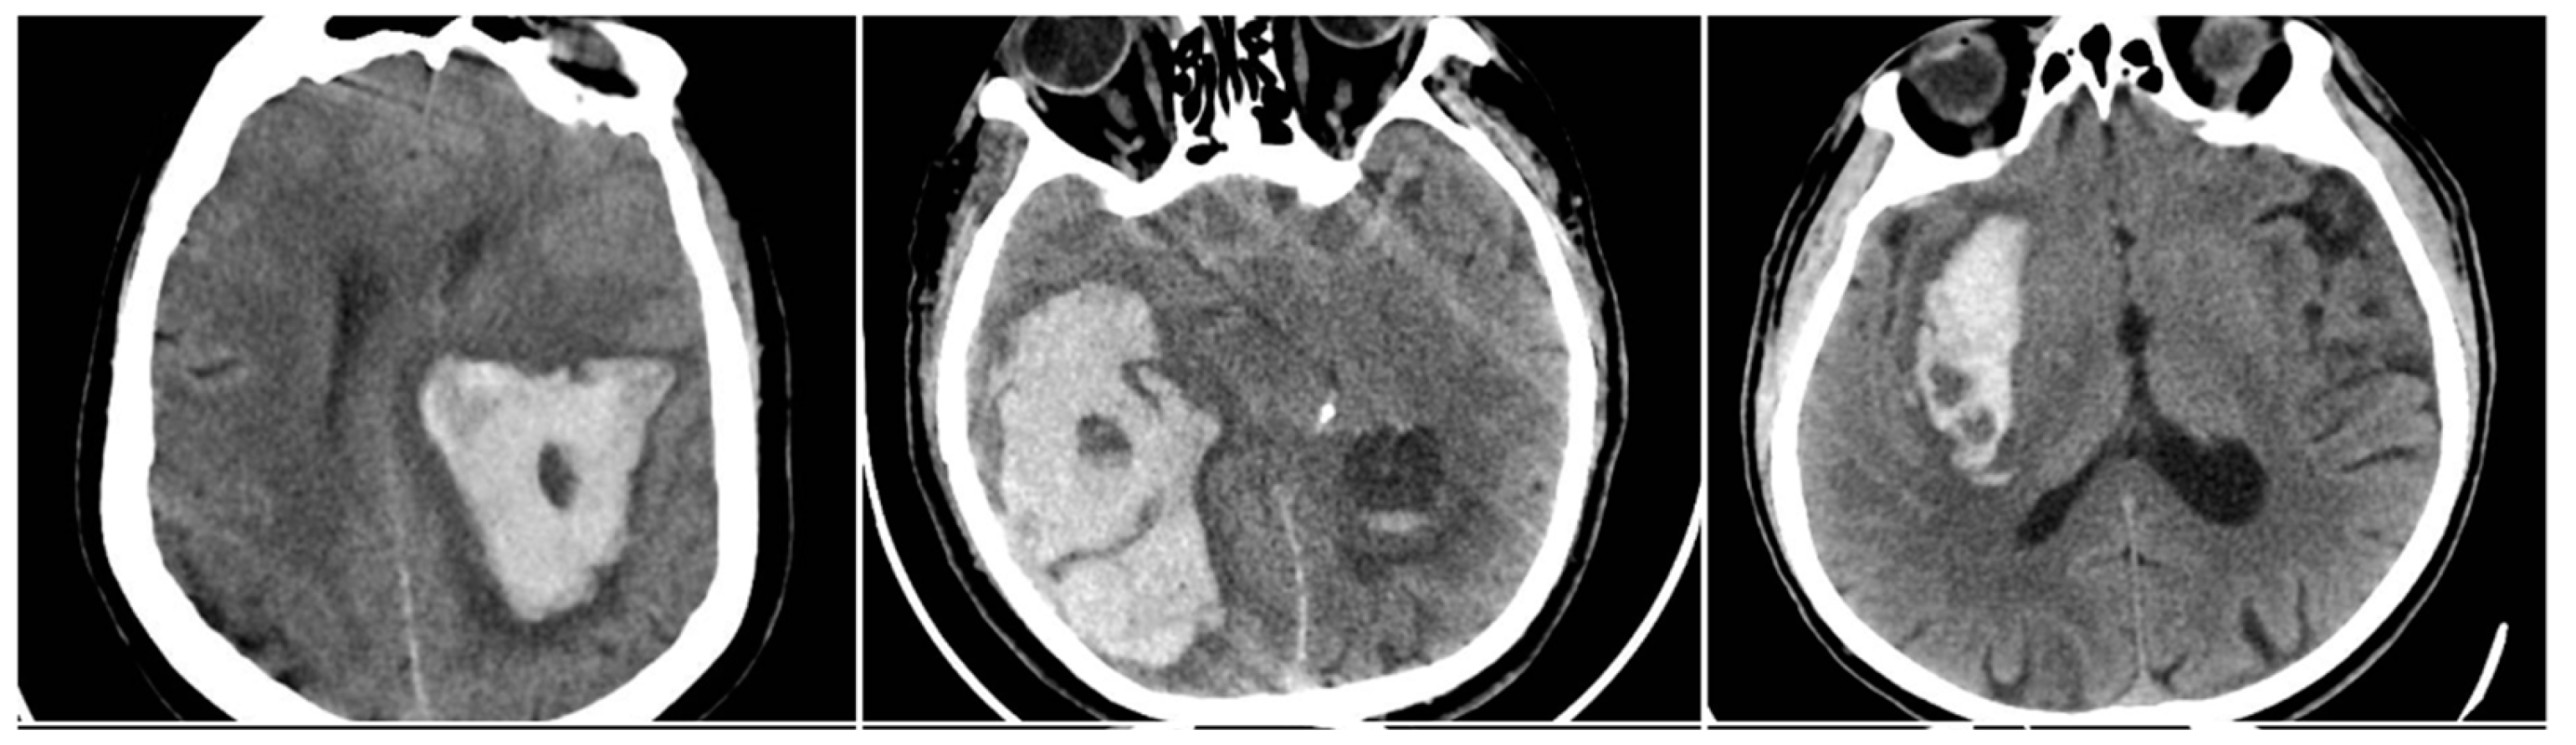

In-hospital mortality analysis demonstrated an even clearer relationship with radiological findings (Figure 6). Patients who died had a mean SUM_BBIS of 1.95, whereas survivors had 0.93 (independent samples t-test p<0.001). At the individual sign level, all four markers appeared markedly more often in non-survivors: BS in 24.8% vs. 11.1% of survivors (p<0.001), BHS in 66.4% vs. 15.4% (p<0.001), IRS in 87.2% vs. 50.8% (p<0.001), and SS in 52.0% vs. 27.2% (p<0.001). Table 3 illustrates these proportions. In pairwise comparisons, the Black Hole Sign had the largest absolute gap between fatal and nonfatal cases (50.9 percentage points), suggesting that a large fraction of fatal ICH cases exhibit pronounced intra-hematoma hypodensity indicative of ongoing or repeated bleeding episodes.

Figure 6. Intracerebral hemorrhage (ICH) from the subgroup with in-hospital mortality, demonstrating a high incidence of NCCT signs.